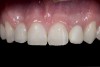

(12.) 15-year-old girl after orthodontic therapy idealized maxillary lateral incisor spaces.

Figure 12

(13.) Deficient ridges in the areas of the missing lateral incisors.

Figure 13

(14.) Occlusal view. Some form of augmentation would be needed if implants were being considered.

Figure 14

Some patients do not want an implant due to the need for surgical intervention, and others may not have enough space for implant placement. A 15-year-old patient presented to the office after completion of orthodontic treatment to idealize the spacing of her teeth and improve her occlusal relationship (Figure 12 through Figure 14). Because both of her maxillary lateral incisors were missing, the patient was wearing a retainer with lateral incisor pontics. She had a busy school schedule, but expressed her desire for a fixed restorative option. All of her options were discussed, and the patient was informed that if she wanted an implant, she would have to wait for at least 3 to 4 years for completion of growth. The patient was not sure if or when she wanted to have an implant placed in the future, especially considering her busy schedule and desire to attend college after high school. Considering her age and the need to be conservative, a single-wing zirconia Maryland Bridge was chosen as the ideal prosthetic replacement option. Because bonding a non-etchable and smooth surface such as zirconia requires chemical adhesion, it was decided to use a modified technique to make the bridge more retentive. One of the ways to improve adhesion of a zirconia bridge is to use an etchable feldspathic ceramic layer on the internal surface of the zirconia retainer.56-58 Unfortunately, it can be difficult to determine the thickness of the ceramic and ensure accurate seating of the restoration.